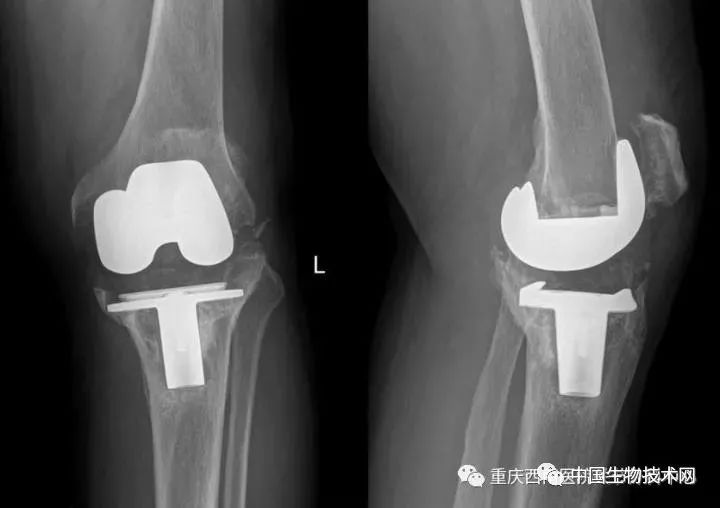

术后X光片

据介绍,各方合作为患者量身定制的3D打印钽金属垫块良好的贴合度和表面粗糙度完美填充了巨大骨缺损,确保了骨缺损后钽金属垫块植入的初始稳定性,表面粗糙多孔的金属骨小梁设计又可以使自体骨快速长入金属孔隙內,从而获得假体与自体骨的长期稳定,手术的操作流程大大简化,手术时间大幅缩减,并减少了手术并发症,也使得假体植入后的长期稳定性得到有效保证。